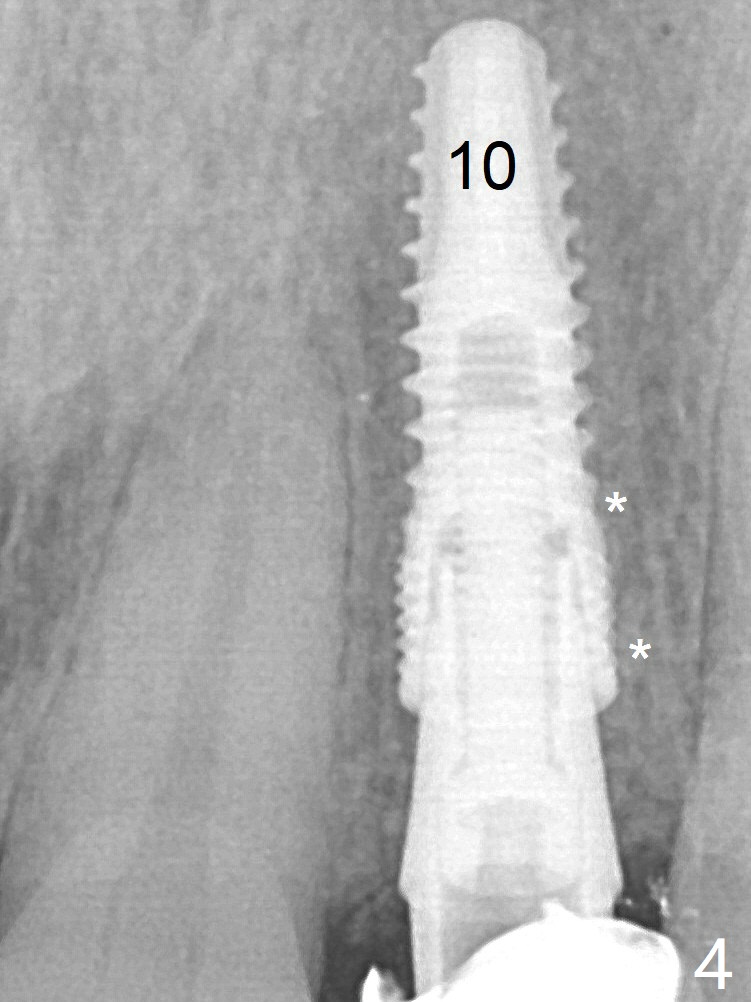

After a 3.8x12 mm SM implant is placed (Fig.4), allograft is packed in the periimplant space (*).  The patient returns for impression 3.5 months postop (Fig.10).